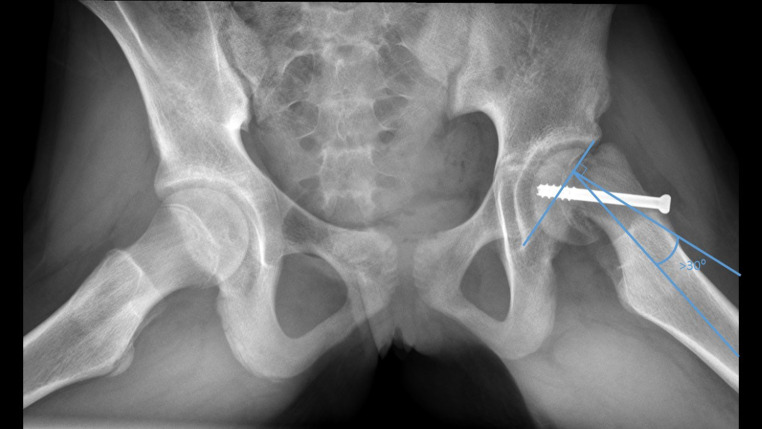

Background: Accurate repositioning of the femoral head in patients with Slipped Capital Femoral Epiphysis (SCFE) undergoing Imhäuser osteotomy is very challenging. The objective of this study is to determine if preoperative 3D planning and a 3D-printed surgical guide improve the accuracy of the placement of the femoral head.

Methods: This retrospective study compared outcome parameters of patients who underwent a classic Imhäuser osteotomy from 2009 to 2013 with those who underwent an Imhäuser osteotomy using 3D preoperative planning and 3D-printed surgical guides from 2014 to 2021. The primary endpoint was improvement in Range of Motion (ROM) of the hip. Secondary outcomes were radiographic improvement (Southwick angle), patient-reported clinical outcomes regarding hip and psychosocial complaints assessed with two questionnaires and duration of surgery.

Results: In the 14 patients of the 3D group radiographic improvement was slightly greater and duration of surgery was slightly shorter than in the 7 patients of the classis Imhäuser group. No difference was found in the ROM, and patient reported clinical outcomes were slightly less favourable.

Conclusions: Surprisingly we didn't find a significant difference between the two groups. Further research on the use of 3D planning an 3D-printed surgical guides is needed.